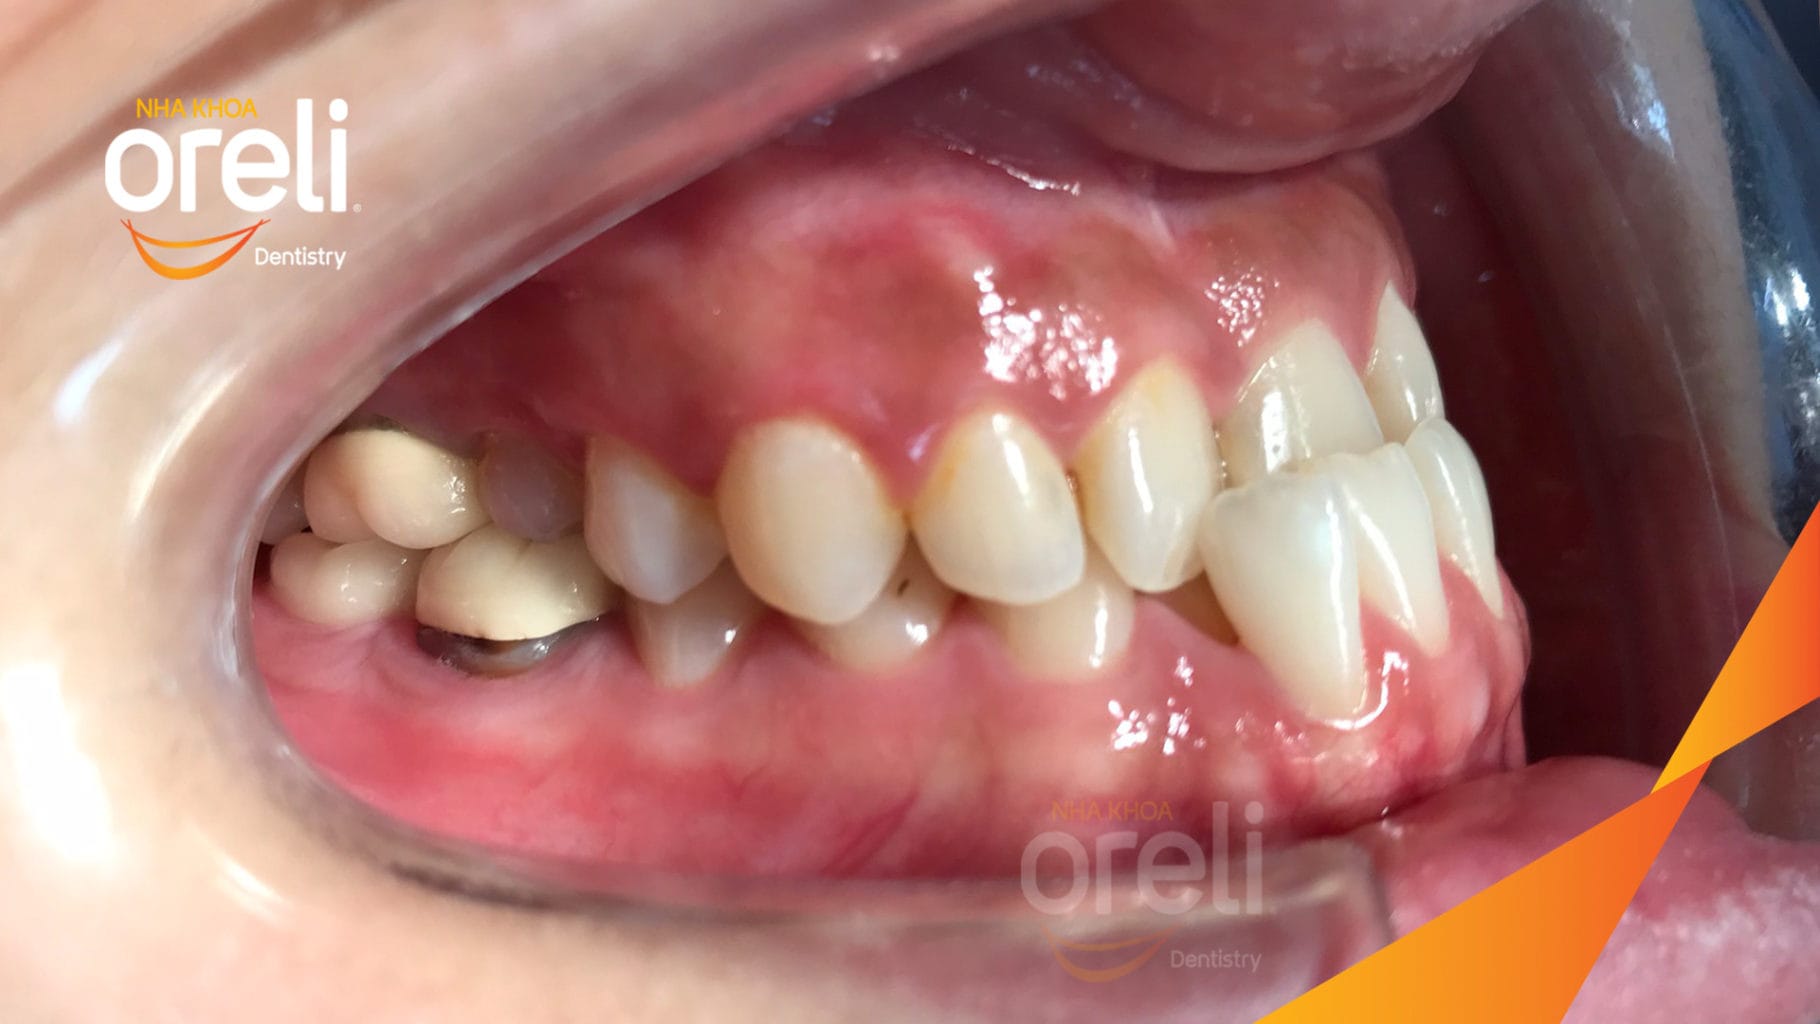

Ca niềng hạng 3 móm di gần răng 78 cho nụ cười đẹp ở Oreli

Ca niềng răng di gần răng 7 8 phục hồi ăn nhai và thẩm mỹ nụ cười. Kết quả thực tế trước và sau điều trị tại Nha khoa Oreli.